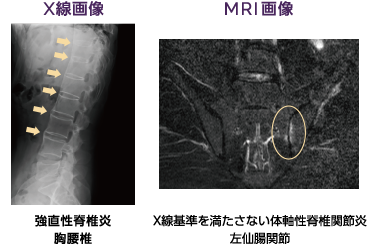

非放射線撮影による軸性脊椎関節炎 (nr-axSpA) は、脊椎および骨盤の仙腸関節 (SI) の慢性炎症状態です。

これは軸性脊椎関節炎 (axSpA) のスペクトルの一部であり、単純 X 線写真 (X 線) で仙腸関節に目に見える損傷がない場合に axSpA を表します。